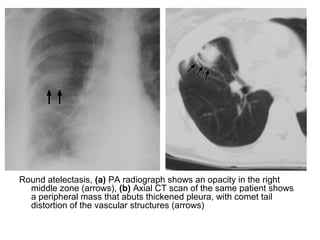

Round atelectasis, (a) PA radiograph shows an opacity in the right

middle zone (arrows), (b) Axial CT scan of the same patient shows

a peripheral mass that abuts thickened pleura, with comet tail

distortion of the vascular structures (arrows)